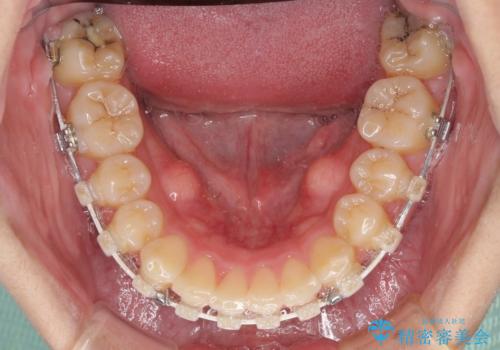

- 矯正装置

- 審美装置

結婚式前には目立つ部分の装置を一時的に外し、結婚式後に装着し直して治療を継続する予定としました。

咬合力が非常に強く、抜歯したスペースがなかなか閉じないであろうことは予想できましたが、思っていた以上に期間がかかりました。